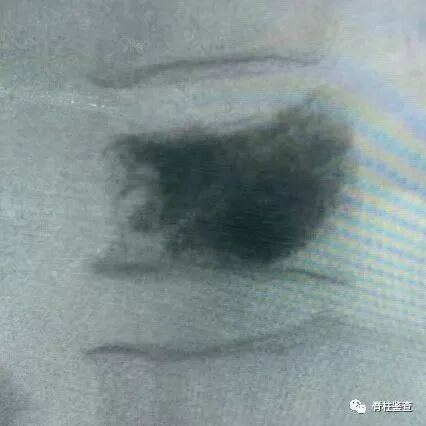

骨质疏松性椎体骨折Kümmell病

骨质疏松性椎体骨折:椎体部分塌陷